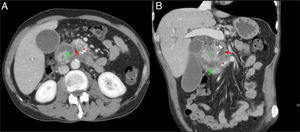

Varón de 60 años con síndrome constitucional. Corte axial (A) y coronal (B) del abdomen con contraste intravenoso en fase portal. Dilatación del conducto pancreático principal (flecha roja, A y B) y presencia de calcificaciones en la cabeza-cuerpo del páncreas (asterisco rojo, A y B), en relación con pancreatitis crónica. Ocupación del surco pancreaticoduodenal (asterisco verde, B) y engrosamiento mural duodenal con lesiones quísticas en su interior (flecha verde, A y B). Hallazgos compatibles con pancreatitis del surco.

Al ser la PS un tipo de pancreatitis crónica, el páncreas suele presentar los cambios crónicos típicos: atrofia con sustitución grasa, calcificaciones o cálculos en el interior del CPP (fig. 4)4,7,10.